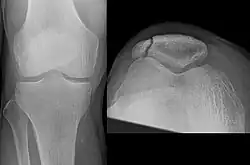

Some people have a normal bipartite patella or two-part patella which can appear as a fracture. The fragment is usually seen in the top outer corner of the patella and can be distinguished from a fracture by being present in both knees.[6]